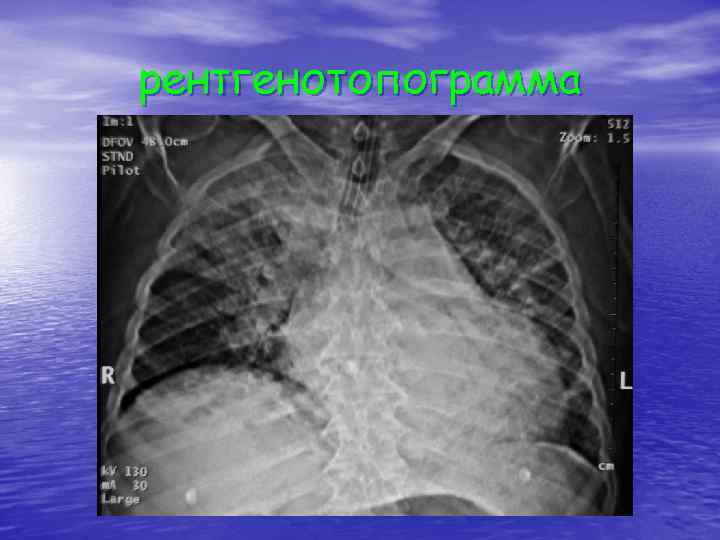

рентгенотопограмма